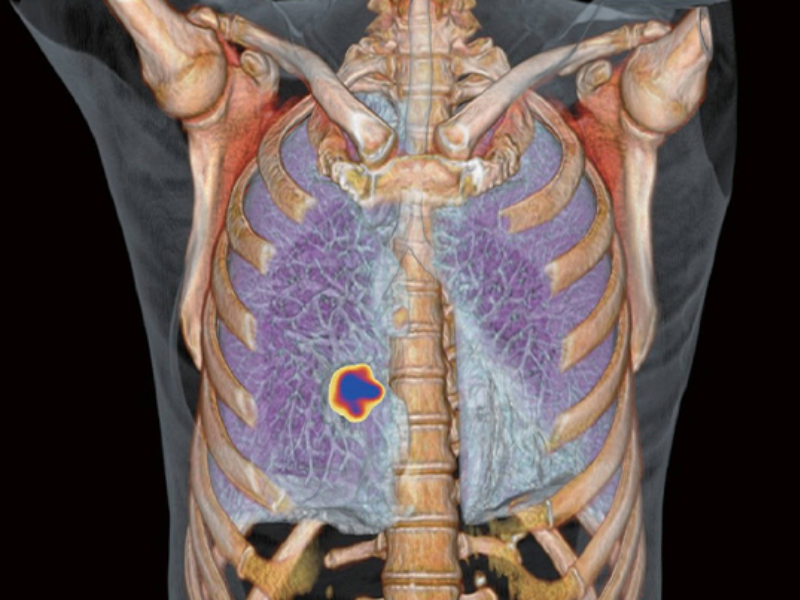

Whole Organ Coverage

Small Lesions Detectability with Gallium-68